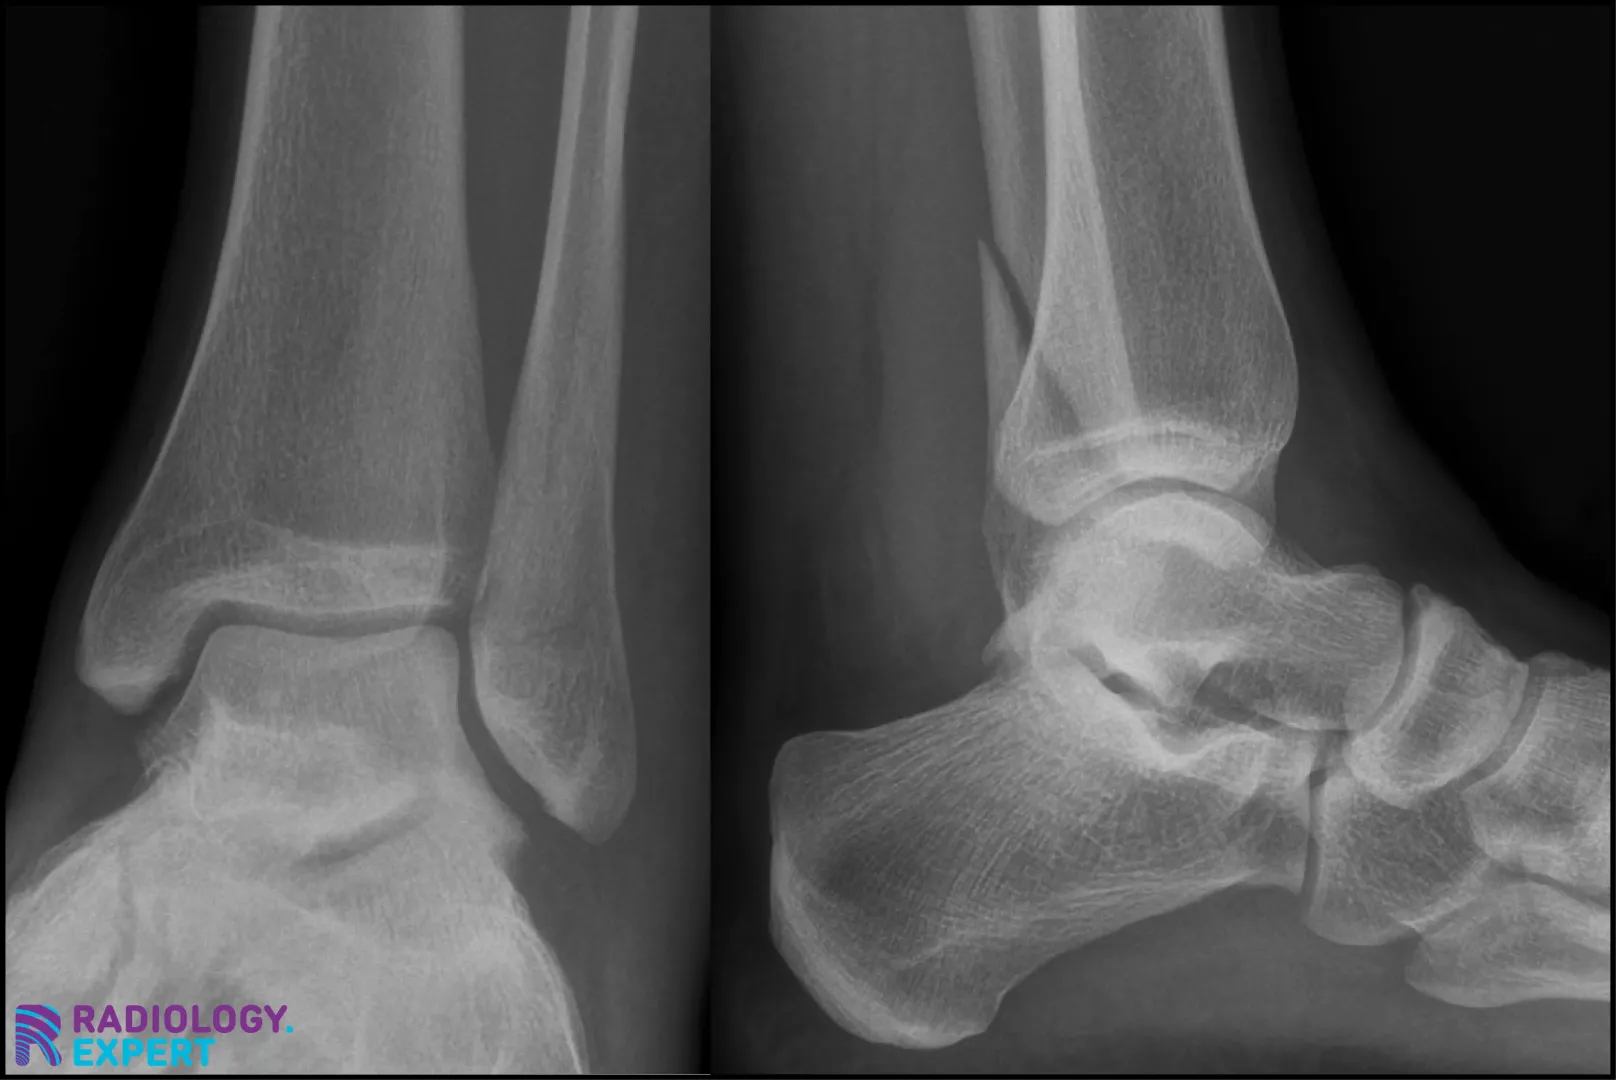

The principle is based on absorption of X-rays by bone (see also X-ray/CT Technique module), which ultimately results in a two-dimensional image. The risk with two-dimensional images is that a fracture line may be invisible if it runs parallel to the direction of the X-ray beam (Fig. 13). Standard protocols therefore include (at least) two projections: often an anteroposterior (AP) view and a lateral view. Depending on the anatomical location, additional projections may be obtained, such as an oblique view for hand or foot fractures, or specific views (e.g., mortise view for ankle fractures). The clinical suspicion and the anatomy of the region of interest determine the choice of projections.

Figure 13. Standard protocols generally include (at least) two projections. Ankle X-ray: the distal fibula fracture is almost invisible on the AP view (left) but clearly visible on the lateral view (right).

Click image to see overlay